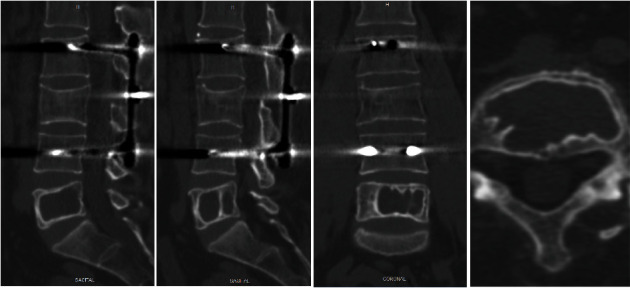

导言:描述一例罕见的成年腰椎椎体单发骨囊肿病例。单发性骨囊肿的定义是含液体的囊性病变。很少有病例描述椎体位置,而不倾向于后弓或椎体。大多数病例采用切除、刮除和/或植骨的方法进行治疗。迄今为止,还没有在椎体位置注射聚甲基丙烯酸甲酯(PMMA)的病例。病例介绍。一名 50 岁的男性患者因腰部疼痛就诊,无外伤史,无神经功能缺损。放射学检查显示,患者在二十年前曾因 L3 骨折而进行过腰椎关节置换术,并植入了 L2-L4 器械。计算机断层扫描(CT)显示,溶蚀性病变几乎占据了 L5 的整个椎体,椎间隙不完整,边缘硬化,皮质无破裂。为了避免在进行磁共振(MR)检查时出现伪影,患者移除了之前的钢制器械,并在同一次手术中经穿刺对 L5 椎体进行了活检。磁共振检查结果和活检结果均与单纯骨囊肿相符。最后,通过使用 PMMA 填充病变部位进行了新的干预。5年的随访结果令人满意,没有腰痛,放射学检查结果也是如此,患者恢复了以往的活动能力:结论:脊柱部位的单纯骨囊肿极为罕见。其诊断需要排除其他病变,并通过影像学检查和活组织检查来确定。治疗方法有切除术、刮宫术、植骨填充术或本例中的PMMA填充术。

Introduction: To describe a rare case of solitary bone cyst in the vertebral body of the lumbar vertebra in an adult patient. The solitary bone cyst is defined as a cystic lesion with liquid content. Few cases have been described in the vertebral location without preference for the posterior arch or vertebral body. Most have been treated with resection, curettage, and/or grafting. No case described to date has been treated with polymethylmetacrylate (PMMA) injection in the vertebral location. Case Presentation. A 50-year-old male patient was consulted for lumbar pain with no traumatic history and no neurologic deficit. The radiological study showed lumbar arthrodesis with L2-L4 instrumentation due to an L3 fracture twenty years earlier. Computed tomography (CT) scan showed a lytic lesion occupying practically the entire vertebral body of L5, with incomplete septum and sclerotic edge, without cortical rupture. The previous steel instrumentation was removed, to avoid the presence of artifacts when performing the magnetic resonance (MR), and a biopsy of L5 vertebra was performed via transpedicular in the same act. The MR study findings and biopsy were compatible with the simple bone cyst. Finally, a new intervention was performed by filling the lesion with PMMA. Follow-up at 5 years was satisfactory without lumbar pain as well as the radiological study and with a return to previous activity.